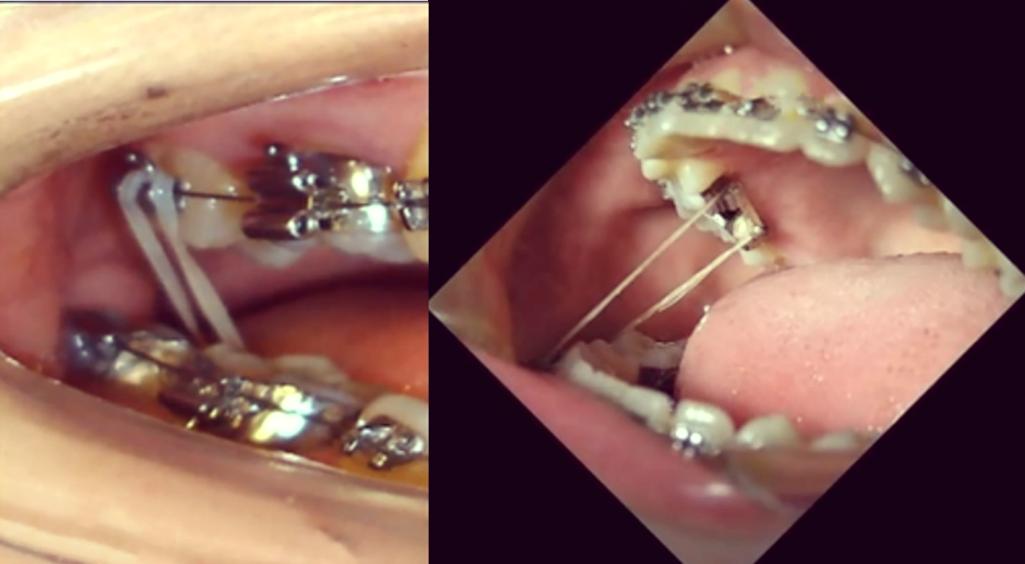

- 橡皮筋: 最常用,将橡皮筋一端挂在尖牙托槽的牵引钩上(或粘在尖牙上的牵引钩上),另一端挂在后牙(如磨牙)的带环或托槽的牵引钩上,通过选择不同的挂钩位置和橡皮筋类型(力量、方向),实现向下向后的合力。

- 托槽: 粘在尖牙上的托槽通常带有牵引钩。

- 额外牵引钩: 有时需要在尖牙牙面额外粘一个小的牵引钩,以便于挂橡皮筋。

- 拉钩: 对于埋伏牙牵引,外科暴露后,医生会在牙冠上粘一个金属拉钩(通常是“眼睑拉钩”或“骨钩”),用于连接牵引装置。